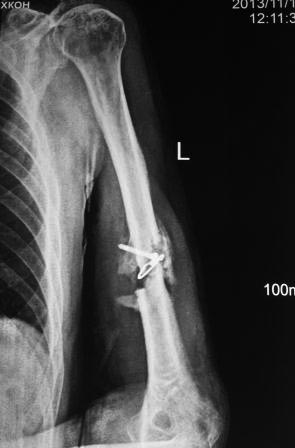

[Ortho] Ложный сустав плечевой кости

Пациент 1942г.р. 4 месяца назад оперирован в экстренном порядке в другом

областном неотложном центре, 20 дней назад гипс снят и направлен к нам.

Пациент активный, оптимист, никогда ничем не болел. Локально: тугой

ложный сустав с варусной деформацией, клиника полного повреждения

лучевого нерва (со слов, до операции также рука висела), контрактура

локтевого сустава, разгибательная контрактура л/з сустава и

пальцев,воспалительных изменений нет. От предложенного БИОС по

финансовым соображениям отказался.

Предварительный план лечения: удаление металлоконструкций,

ревизия лучевого нерва (возможно, пластика нерва), освежение концов до

появление "росы", и адаптация концов возможно по типу "русского замка",

фиксация либо аппаратом Илизарова, либо пластиной ( у нас обычные

пластины ЦИТО типа DCP), возможно укорочение на 2-3 см, но это

для плеча большого значения не имеет, главное - ранняя и усиленная